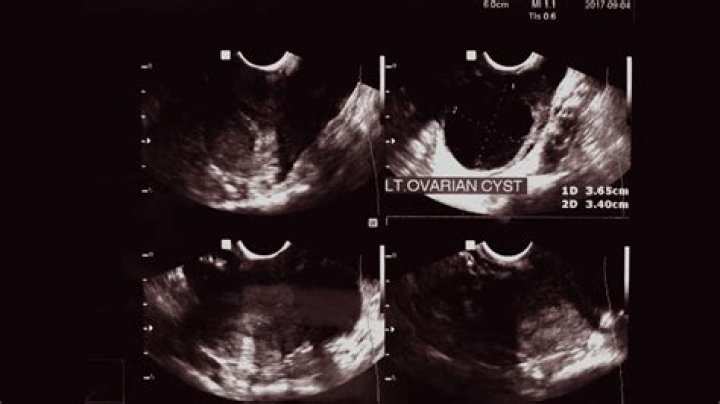

Can a cyst be missed on ultrasound?

Can an ovarian cyst last for years?